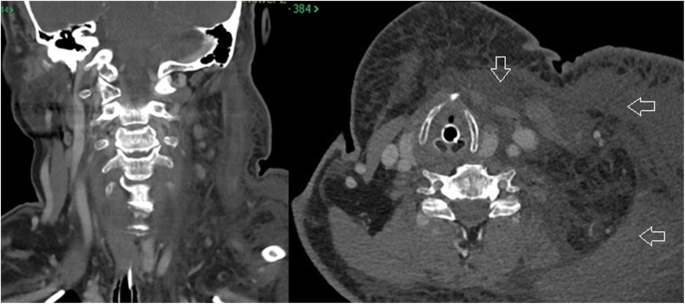

Anesthesia evaluation on the day of surgery was performed and her neck was recorded as “unremarkable.” She was assigned an American Society of Anesthesiologists (ASA) score of 2. On the day of surgery, she was easily intubated with an endotracheal tube in the supine position and then placed in the standard lateral decubitus position for arthroscopic shoulder surgery. Exam under anesthesia was performed followed by a diagnostic shoulder arthroscopy. Normal saline was fed into a Stryker CrossFlow® Integrated Arthroscopy Pump (Stryker Endoscopy, San Jose, CA, USA) set at 25 mmHg initially. Epinephrine was not added to the irrigation fluid. Shortly after beginning the case, the arthroscopic fluid pressure was raised to 35 mmHg to aid in visualization where it remained for the duration of the case. No lavage cycles were utilized. Standard posterior, anterosuperior and anteroinferior portals were placed as well as a lateral working portal. She was found to have a type 1 superior labrum anterior to posterior (SLAP) tear, degenerative changes in the anterior, inferior and posterior labrum, a subscapularis tear in the upper one third which was retracted medially, and a complete supraspinatus tear. A biceps tenotomy was performed followed by rotator cuff repair of the subscapularis and supraspinatus tears utilizing suture anchors. Bone quality was remarkably poor with pull-out of multiple suture anchors during the rotator cuff repair adding to surgical complexity and time. Total operative time was 3 h and 53 min. Upon completion of the case and removal of the surgical drapes, significant unilateral face and neck swelling was noted on the side of the operative shoulder (the non-gravity dependent side). Upon consultation with the anesthesia providers the decision was made to obtain a computed tomography (CT) scan for visualization of the soft tissues surrounding the airway, with a plan to leave the patient intubated overnight. The CT demonstrated diffuse soft tissue edema in the subcutaneous tissues of the neck, chest and face. The airway was deviated at the level of the trachea due to the paratracheal edema. There was no focal collection or extravasated contrast indicative of a hematoma or vascular injury (Fig. 2).